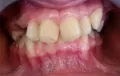

Ретенированный зуб можно вытянуть с помощью брекет-системы, а также не исключено, что он прорежется самостоятельно. И его останется установить на свое место.

По снимку данный зуб - постоянный клык.